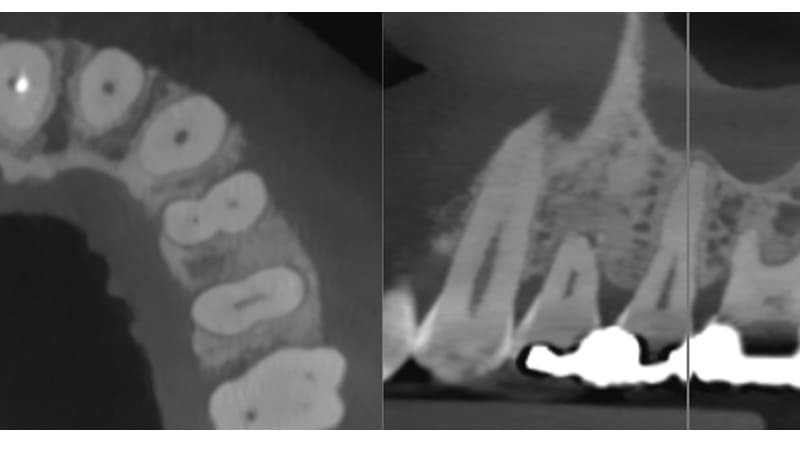

症例①:右下の奥歯が腫れる

| 治療科目 | 歯周組織再生療法(リグロス使用) |

|---|---|

| 主訴 | 右下の奥歯が腫れる |

| 治療期間 | 1年 |

| 治療費 | 2〜3万円程度 |

| 治療内容 | 浸潤麻酔後、歯肉を剥離し歯石除去する。リグロスを塗布し緊密に縫合。3ヶ月後に再評価。 |

| 治療のリスク | リグロスの特性上かなり腫れることがあります。 まれに脂肪腫をつくることがあります。 角化歯肉の状態により再度感染を起こす可能性があり、遊離歯肉移植の併用が必要なこともあります。 清掃方法によって再感染する可能性があり、定期的な通院でチェックしていく必要があります。 |